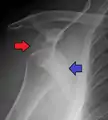

A diagnosis of shoulder dislocation is often suspected based on the person's history and physical examination. Radiographs are made to confirm the diagnosis. Most dislocations are apparent on radiographs showing incongruence of the glenohumeral joint. Posterior dislocations may be hard to detect on standard AP radiographs, but are more readily detected on other views. After reduction, radiographs are usually repeated to confirm successful reduction and to detect bone damage. After repeated shoulder dislocations, an MRI scan may be used to assess soft tissue damage. In regards to recurrent dislocations, the apprehension test (anterior instability) and sulcus sign (inferior instability) are useful methods for determining predisposition to future dislocation.

A Hill–Sachs lesion is an impaction of the head of the humerus left by the glenoid rim during dislocation.[6] Hill-Sachs deformities occur in 35–40% of anterior dislocations. They can be seen on a front-facing X-ray when the arm is in internal rotation.[9] Bankart lesions are disruptions of the glenoid labrum with or without an avulsion of bone fragment.

Anterior dislocation of the right shoulder. AP X ray